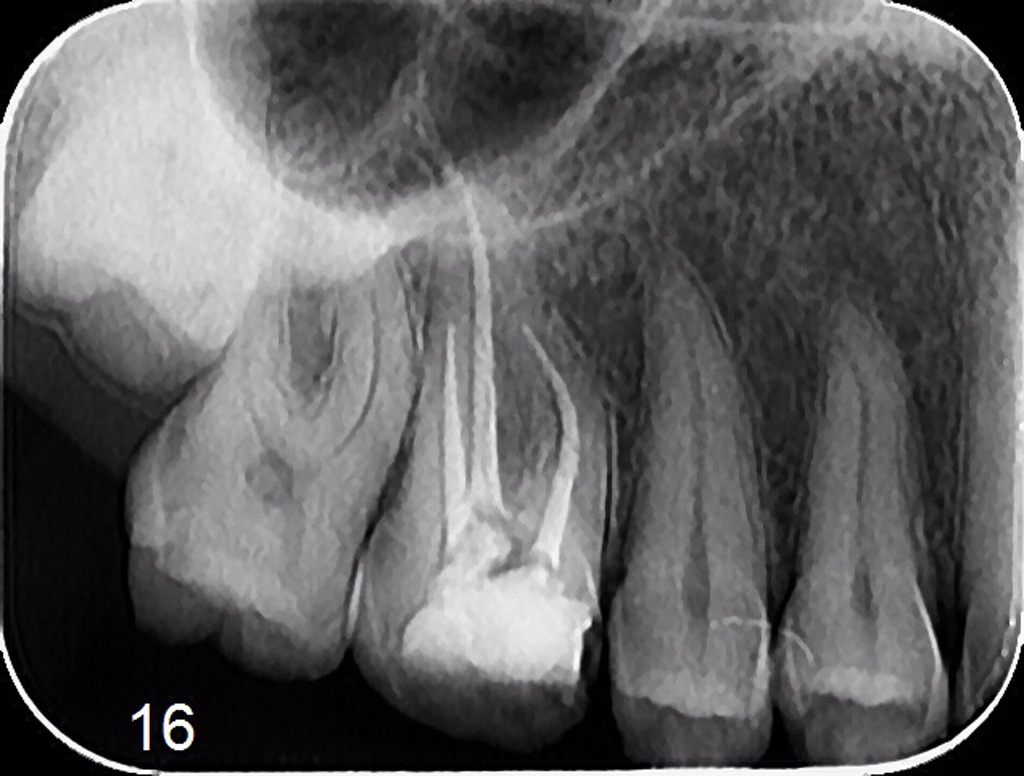

Lečenje zuba podrazumeva postupak uklanjanja nerva iz samog zuba. Naš tim se edukavao iz oblasti savremenih principa endodontske terapije i mašinske endodoncije kako bi svojim pacijetima ponudili najkvalitetnije usluge iz navedene oblasti.

Znanje i aparatura koju posedujemo omugućuje nam da obradu kanala korena zuba sprovodimo uoptrebom mašinskih rotirajućih instrumenata (ProtaperNext), irigansa propisanih od strane evropske asocijacije endodonata i savremnih tehnika punjenja kanala korena. Na taj način zubi su besprekorno izlečeni i traju dug vremenski period.